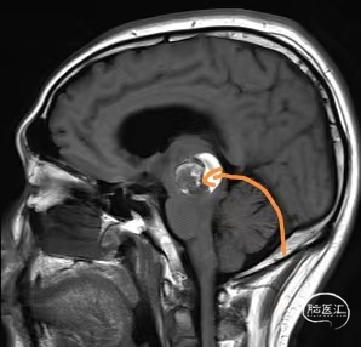

术前MRI检查

术前MRI检查提示左侧丘脑中脑海绵状血管瘤并卒中,梗阻性脑积水;

本例患者磁共振检查清晰显示病变位于左侧丘脑中脑区域,且位于丘脑内下方向中脑顶盖延续,病变的上部、前部、外侧部都有重要的神经组织,因此,手术从上方、前方、外侧方向切除病变均难以实施;